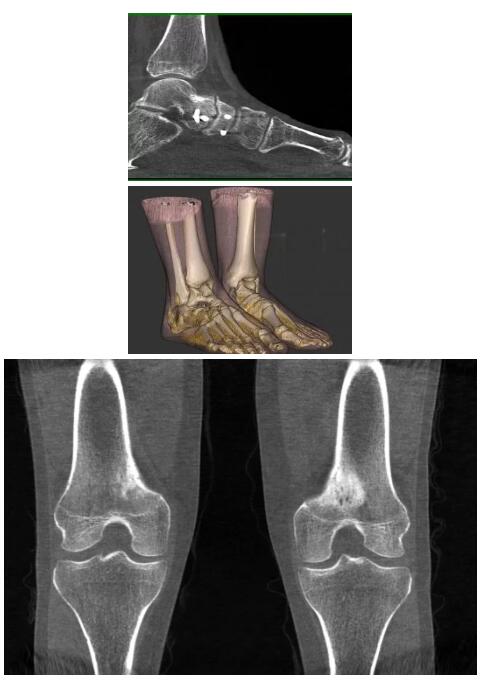

比如上面這款專用于足部和踝部掃查的CT成像系統(tǒng),患者在進行CT掃查時只需要站在上面即可,雙腳站或者單腳站都可以,當(dāng)然,如果患者不是那么方便站著做完CT掃查,也可坐在上面。

這款CT掃查系統(tǒng)自帶屏蔽裝置,它的體積非常小,僅需要極小的空間即可,并不像常規(guī)CT那樣需要一間單獨的檢查室。此外,這種CT掃查的速度非???,僅需30秒左右可以完成檢查,輻射劑量相對常規(guī)的CT要少許多,尤其適合醫(yī)院的骨科使用。

而患者站著做足部或者踝部做CT檢查還有個好處是,可以檢查患者在負(fù)重的情況下,骨關(guān)節(jié)的真實情況,而躺著做CT掃查時未必能看出來。負(fù)重CT掃查特別是對于受傷的運動員或者舞蹈員來說意義更大,能夠更準(zhǔn)確地評估傷情,幫助他們盡早復(fù)原。

以上介紹的CT均來自國外同一家公司,這些CT均配置了可視化軟件,可以進行切片、3D重建以及大型CT附帶的所有典型的操作功能。

以下是這些“特立獨行”的CT所拍出來的圖像: